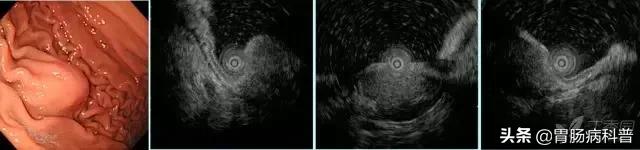

图 1

图 1 A-B 胃体上后壁间质瘤;D-E 胃窦前壁间质瘤,以上病变均起源于黏膜第四层,与周围黏膜界线清晰,与肌层延续处可观察到「喇叭口」样结构(箭头所示)